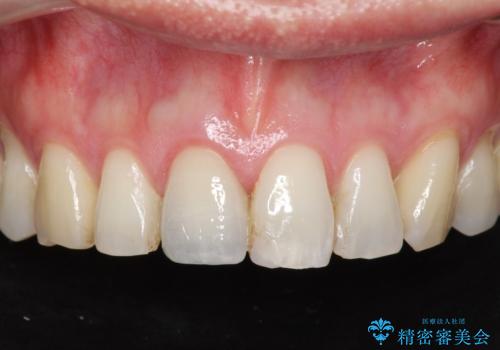

目立つ前歯の審美性が改善したことで見た目を気にせず笑えるようになった。との嬉しい感想をいただくことができました。